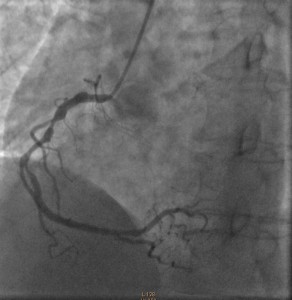

Cardiac catheterization revealed 80% to 90% proximal and mid-stenoses in the left anterior descending (LAD) artery, the left circumflex (LCX) artery, and the right coronary artery (RCA). TIMI 3 flow was noted throughout. The LAD and LCX arteries are shown in the left image below; the RCA is shown on the right.